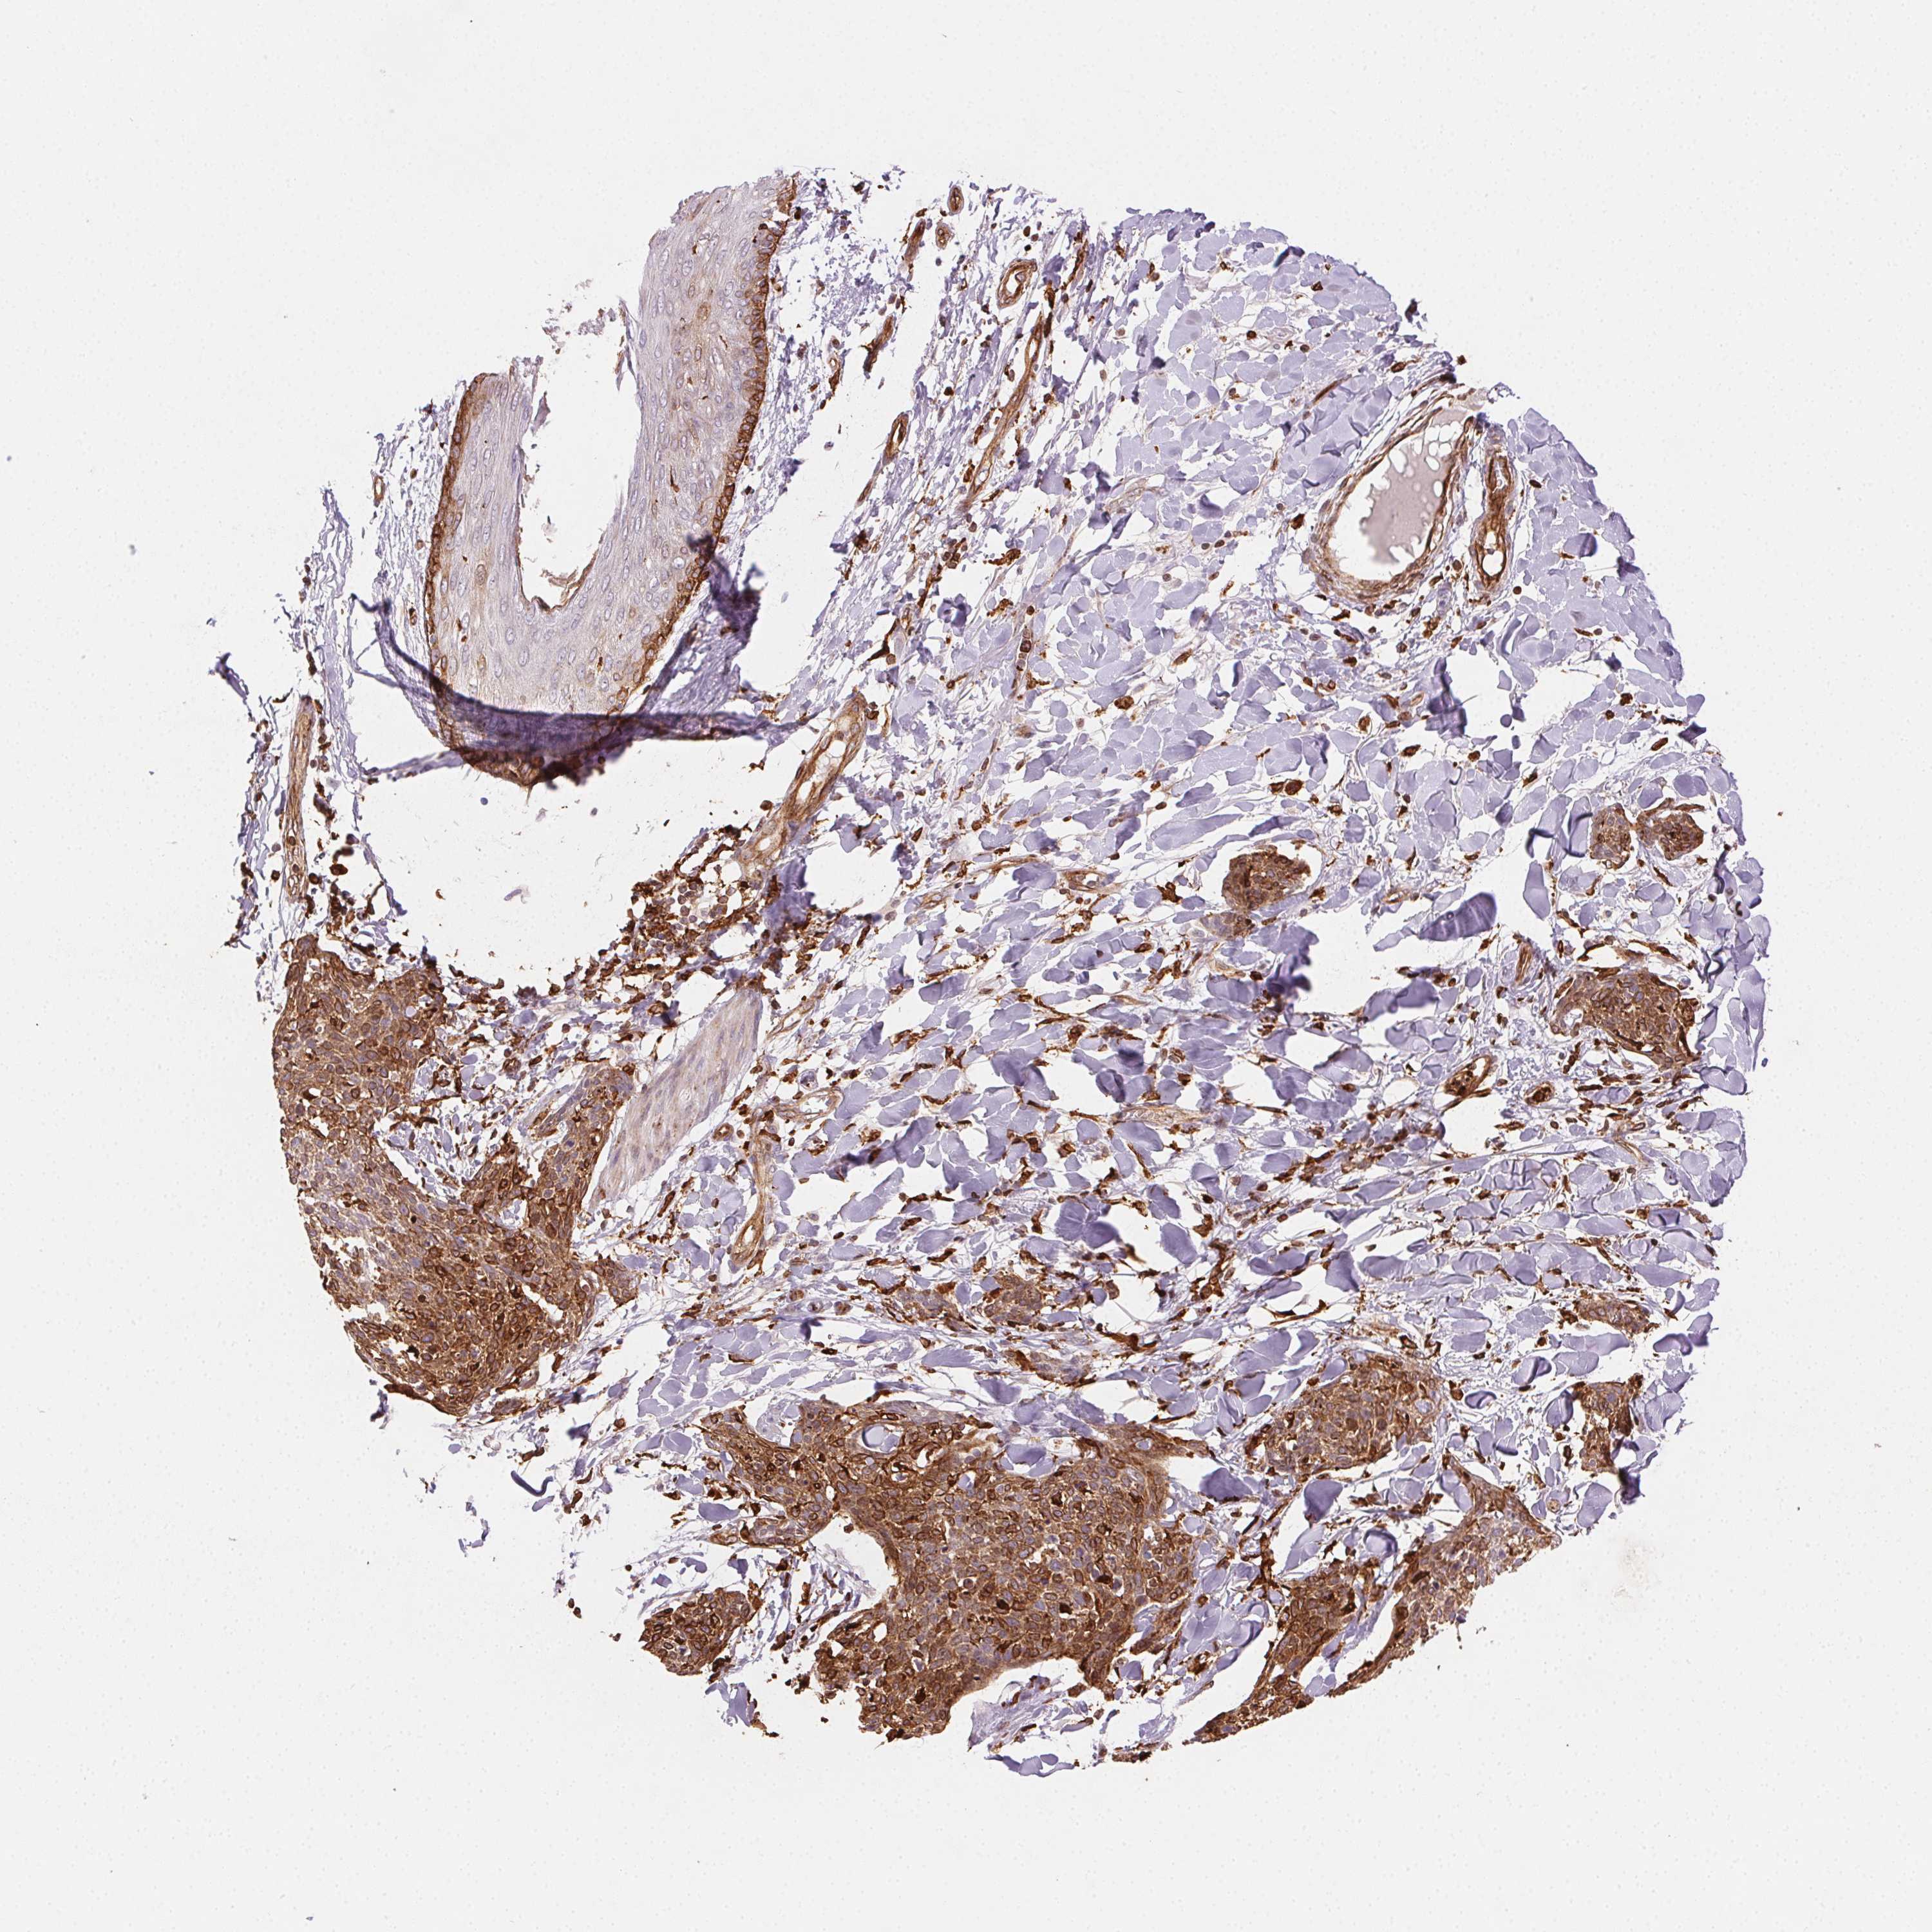

SKIN CANCER - Protein expressioni

A mouse-over function shows sample information and annotation data. Click on an image to view it in a full screen mode. Samples can be filtered based on level of antibody staining by selecting one or several of the following categories: high, medium, low and not detected. The assay and annotation is described here.

Antibody staining in the annotated cell types in the current human tissue is reported as not detected, low, medium, or high, based on conventional immunohistochemistry profiling in selected tissues. This score is based on the combination of the staining intensity and fraction of stained cells.

Each image is clickable and will lead to virtual microscopy that enables deeper exploration of all samples and also displays staining intensity scores, fraction scores and subcellular localization as well as patient and tissue information for each sample.

Antibody HPA029013

Basal cell carcinoma